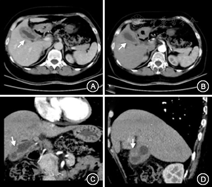

(1)病例特点:患者男性,69岁,因"胸闷不适5 d"于2015年8月6日就诊我院胸外科,正电子发射计算机断层显像(PETCT)提示:"肝右叶稍低密度肿块,考虑恶性可能大"(图1),以"肝占位"转入我科。既往史:否认肝炎病史。查体:无明显阳性体征。实验室检查:肿瘤标志物甲胎蛋白(AFP)、癌胚抗原(CEA)、CA19-9及其他生化检查未见明显异常。Child-Pugh分级为A级。B超及腹部增强CT均考虑恶性(图2,图3)。(2)治疗:手术行肝部分切除术,术中冰冻回报:考虑肝炎性肌纤维母细胞瘤。术后大体标本:呈黄白色、鱼肉状、质地较硬,似有包膜。(3)术后病理诊断为肝炎性肌纤维母细胞瘤。(4)预后:术后7个月门诊复查未见明显复发(图4),术后电话随访18个月未见明显复发表现,恢复良好。